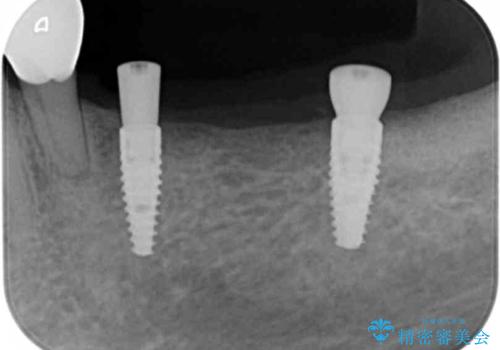

臼歯部の欠損 インプラント補綴

- 「奥歯がたくさん無くなってしまい、食事が楽しめるようにしっかりとかめるようにしてほしい。」という希望で来院されました。

入れ歯かインプラント治療の選択肢をご案内ししっかりと咀嚼機能を回復できる、インプラント治療を希望されました。

骨の量が比較的十分に保たれていたため、インプラントを埋入し1ヶ月後には仮歯を入れてしっかりと咬合機能を回復することができました。